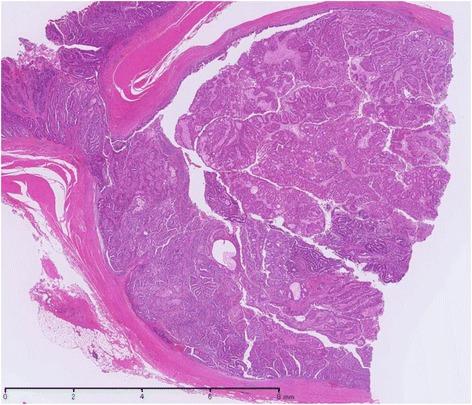

A colonoscopy that was performed on a 69-year-old man because of bloody stool and an elevated carcinoembryonic antigen (CEA) level revealed a polypoid lesion at the right ureterosigmoid anastomosis site 29 years after the patient's ureterosigmoidostomy. Endoscopic resection was performed, and the lesion was diagnosed as adenocarcinoma. Seven years later (36 years after ureterosigmoidostomy), an elevated lesion was detected at the left ureterosigmoid anastomosis site by colonoscopy performed after detection of high CEA levels. Biopsy revealed an adenocarcinoma that was immunohistologically positive for CDX2; sigmoidectomy and ureterectomy were subsequently performed. The pathological diagnosis of the second tumor was adenocarcinoma arising in the ureterosigmoid anastomosis site and invading the left ureter.

一名69岁男性因便血和癌胚抗原(CEA)水平升高接受结肠镜检查,结果显示在患者输尿管乙状结肠吻合术后29年,右侧输尿管乙状结肠吻合部位有一个息肉样病变。进行了内镜切除,病变被诊断为腺癌。7年后(输尿管乙状结肠吻合术后36年),在检测到CEA水平升高后进行结肠镜检查,发现左侧输尿管乙状结肠吻合部位有一个隆起病变。活检显示为腺癌,免疫组化检测CDX2呈阳性;随后进行了乙状结肠切除术和输尿管切除术。第二个肿瘤的病理诊断为起源于输尿管乙状结肠吻合部位并侵犯左侧输尿管的腺癌。